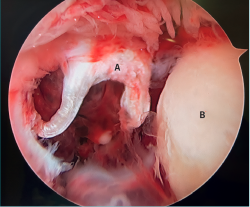

- La letra pi en el tobillo